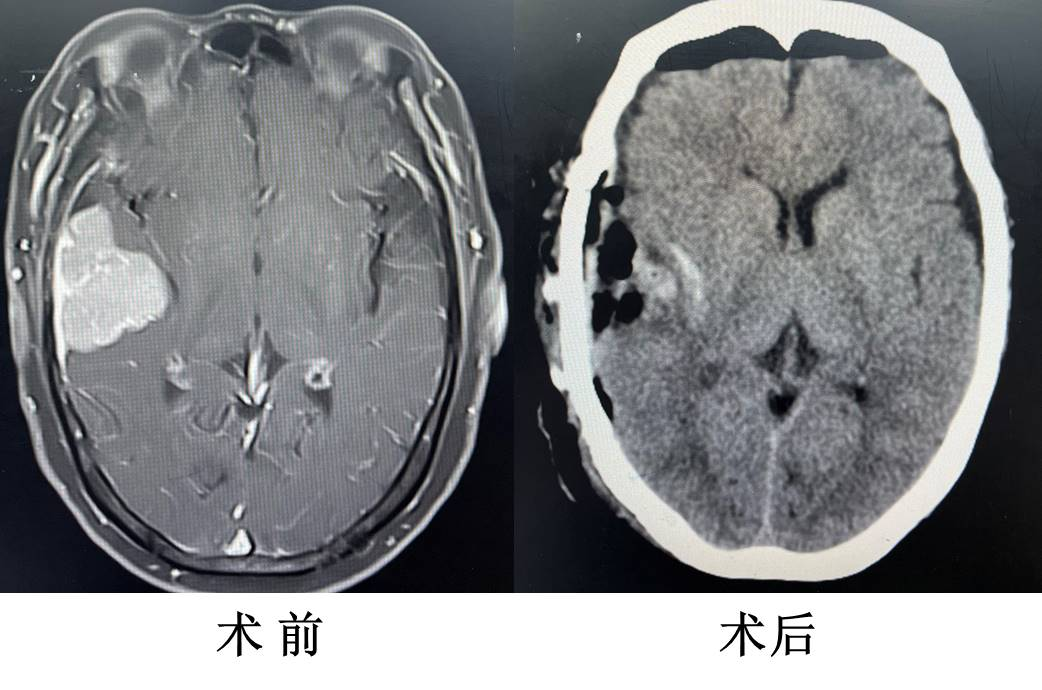

病例二:颞部巨大脑膜瘤的显微镜下肿瘤全切

该例手术应用神经外科显微镜行显微外科手术切除,术中精准操作,精确分离肿瘤组织,保护正常脑组织,避免术后神经功能缺损症状。该患者术后次日拔除引流管、尿管并下床活动,四肢活动灵便,言语清晰,无神经功能缺损。